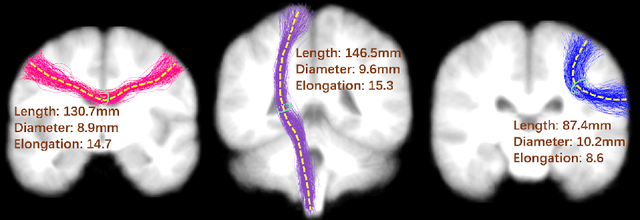

Abstract:Neuroimaging measures of the brain's white matter connections can enable the prediction of non-imaging phenotypes, such as demographic and cognitive measures. Existing works have investigated traditional microstructure and connectivity measures from diffusion MRI tractography, without considering the shape of the connections reconstructed by tractography. In this paper, we investigate the potential of fiber tract shape features for predicting non-imaging phenotypes, both individually and in combination with traditional features. We focus on three basic shape features: length, diameter, and elongation. Two different prediction methods are used, including a traditional regression method and a deep-learning-based prediction method. Experiments use an efficient two-stage fusion strategy for prediction using microstructure, connectivity, and shape measures. To reduce predictive bias due to brain size, normalized shape features are also investigated. Experimental results on the Human Connectome Project (HCP) young adult dataset (n=1065) demonstrate that individual shape features are predictive of non-imaging phenotypes. When combined with microstructure and connectivity features, shape features significantly improve performance for predicting the cognitive score TPVT (NIH Toolbox picture vocabulary test). Overall, this study demonstrates that the shape of fiber tracts contains useful information for the description and study of the living human brain using machine learning.